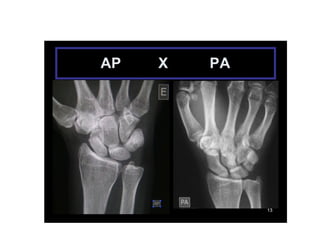

INCIDÊNCIAS PUNHO E MÃO

• #6 A mesma fratura. Uma vista em ap e outra em perfil. Isso mostra que a mesma imagem toma formas diferentes dependendo da incidência. Por isso é importante ter duas incidências no mínimo, pois elas se complementam